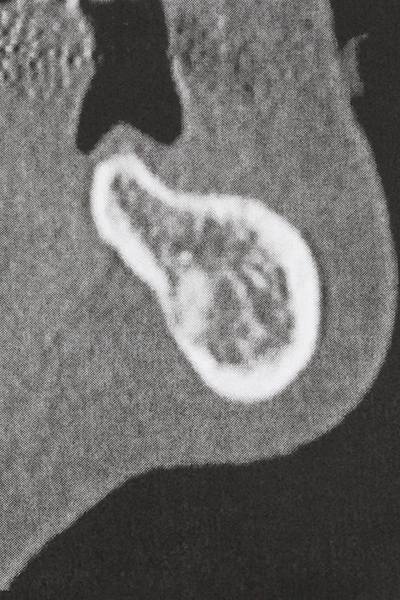

Fig. 17: Tomografía computarizada de un osteoma de crecimiento progresivo ...

Fig. 17b: justo al lado del canal alveolar con irritación nerviosa (vista lateral y coronal).

Fig. 18: Preparación de una tapa cortical con la sierra ósea piezoeléctrica (Piezomed, W&H).

Si es preciso realizar intervenciones quirúrgicas en las que el hueso está en contacto directo con estructuras sensibles, como son los vasos sanguíneos o los nervios, los instrumentos rotativos presentan un enorme potencial de provocar lesiones iatrogénicas. Así, precisamente en la representación de nervios después de una lesión iatrogénica, o en el transcurso de la lateralización de un nervio para resecciones, reconstrucciones o incorporación de implantes, los equipos piezoeléctricos pueden resultar muy útiles para preparar la tapa ósea y retirar las partes de tejido duro cercanas al nervio (fig. 17-20). Por lo general, un ligero contacto del cordón nervioso con el inserto piezoeléctrico no tiene consecuencia alguna; ahora bien, un procedimiento poco cuidadoso con movimientos tipo sierra o piezas de trabajo sobre la base ósea aún existente puede provocar lesiones nerviosas temporales o incluso permanentes. Con todo, el riesgo de sufrir una lesión de este tipo se considera significativamente inferior que en los casos en los que se utilizan sierras y fresas (Pereira, Gealh et al. 2014).